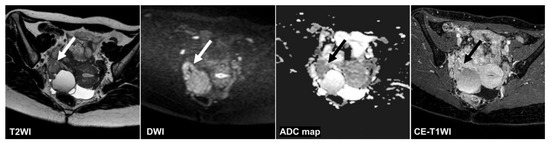

Figure 4, Figure 5 and Figure 6 show the test images of three cases in this study with different interpretations by the CNN and radiologists including the confidence value. Figure 4 and Figure 5 show the cases in which the CNN was able to make the correct diagnosis, although the radiologists had a high rate of false-negative diagnoses. Figure 4 shows a tumor with a slight signal difference between the solid components and the background on the T2WI, DWI, and ADC map. Figure 5 shows a non-malignant tumor containing components that were difficult to distinguish between solid components and mucus on the T2WI; however, the CNN diagnosed it as a non-malignant tumor. Figure 6 shows a case in which the CNN and the radiologists showed false negatives on the sequences other than the DWI, and as for the radiologists, it was assumed that the misdiagnosis was due to the difficulty in distinguishing the solid component of the ovarian tumor from the intestinal tract.

Figure 6.

A 28 year old woman with high-grade serous carcinoma. None of the CNNs or the three radiologists could diagnose malignant tumors on the T2WI and the ADC map (CNN confidence value: malignant = 0.0% on the T2WI; malignant = 1.5% on the ADC map). Only reader 3 could diagnose a malignant tumor on the CE-T1WI (CNN confidence value: malignant = 0.0%). In contrast, the CNN and all radiologists could diagnose malignant tumors on the DWI (the CNN confidence value; malignant = 99.9%). It seemed it was difficult to distinguish the tumor (arrow) from the intestinal tract. ADC: apparent diffusion coefficient; CE-T1WI: contrast-enhanced T1-weighted imaging; CNN: convolutional neural network; DWI: diffusion-weighted imaging; T2WI: T2-weighted imaging.